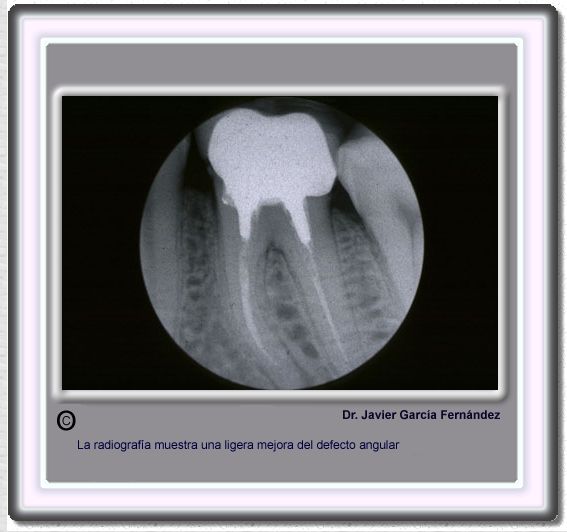

image 819